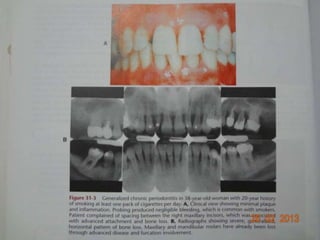

B. Generalized periodontitis - 30% or more of

the sites assessed in the mouth

demonstrate attachment loss & bone loss.

Classification of chronicperiodontitis based on disease distribution A. Localized periodontitis - less than 30% of the sites assessed in the mouth demonstrate attachment loss & bone loss. B. Generalized periodontitis - 30% or more of the sites assessed in the mouth demonstrate attachment loss & bone loss.